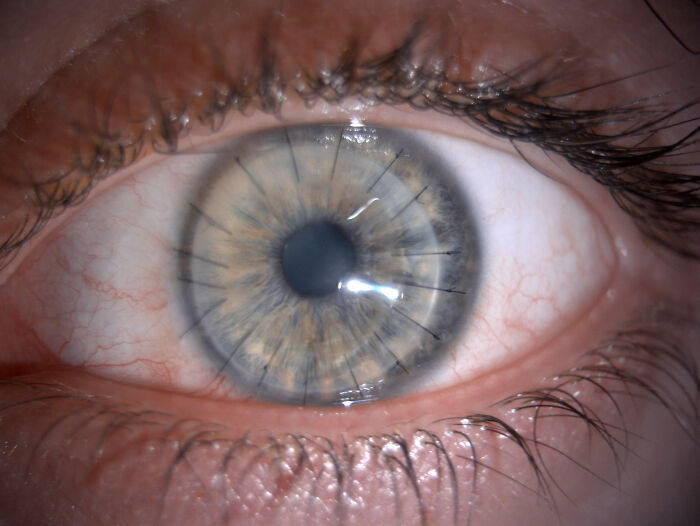

#4 Transplantácia rohovky a 17 stehov, ktoré zostali v oku